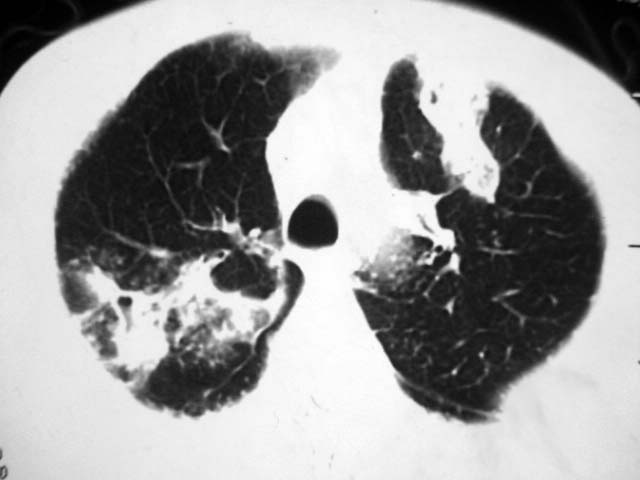

2、双肺见多发片状及结节状高密度影,大多数病灶中心均见“空泡征”。

结果:两肺继发性肺结核并曲霉菌感染。